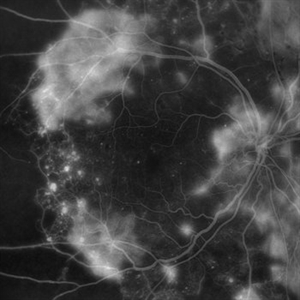

PROLIFERATIVE DIABETIC RETINOPATHY

EARLY PHASE FLUORESCEIN ANGIOGRAPHY OF A 50 YEAR OLD MALE WITH PROLIFERATIVE DIABETIC RETINOPATHY

Photographer: Dr. Akansha Sharma-Retina Foundation, Ahmedabad

Condition/keywords: florid type PDR, proliferative diabetic retinopathy (PDR)

LATE PHASE FLUORESCEIN ANGIOGRAPHY OF A 50 YEAR OLD MALE WITH PROLIFERATIVE DIABETIC RETINOPATHY